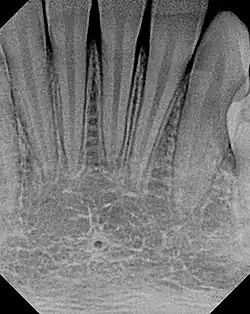

The small lingual foramen (black "hole" in lower portion of picture) as seen on a periapical radiograph of the anterior mandible.

The lingual foramen is a small midline opening on the posterior aspect of the symphysis of the mandible, just above the mental spine. The lingual foramen gives passage to a single small artery formed by the union of two branches of the sublingual arteries (each sublingual artery contributing a single branch).[1]